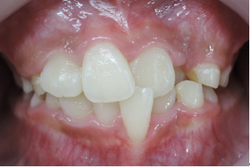

歯並びの悪い症例

口腔機能を順調に発育発達させる為には早期治療が効力を発揮します。

多数の治療法がありますが、当院ではブラケットという矯正装置を歯に装着する事で、上下顎骨の大きさと、咬み合わせの高さを改善していきます。

前歯がクロスしていて将来、口腔機能に悪影響を及ぼす事となります。

①前歯のクロスを改善するためには咬み合わせを高くする必要があります。

当矯正歯科医院では上顎の乳臼歯にレジンを盛る事で、クロスした前歯の被蓋(前歯の咬み合わせ)を改善していきます。

前歯のクロスが改善されて治療しやすくなっています。

その後、ブラケット装着を使用して上顎骨の拡大を始めます。

上顎骨の拡大を始めてから、下顎骨の拡大を始めます。

この上下顎骨の拡大と咬み合わせの高さの改善を1年6ヶ月間、治療を続けます。

すると、治療前と治療後は以下の様に変わります。